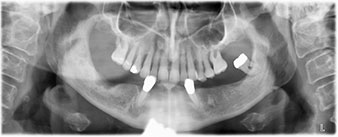

Una vez transcurrido el tiempo necesario para la integración ósea, puede llevarse a cabo la impresión definitiva del implante para realizar la prótesis definitiva de manera acorde (figs. 19 y 20). En este paso, el responsable del tratamiento y el paciente pueden decidir conjuntamente si es preferible un revestimiento cerámico o plástico y una estructura de zircón o de metal. En este caso, dado que el pronóstico de la dentición del maxilar superior era poco claro y la pieza dental 24 estaba elongada, el equipo del Dr. Pascu se decidió por un revestimiento de plástico, ya que, por lo general, es mucho más fácil de ajustar y puede adaptarse a la nueva situación del maxilar superior.